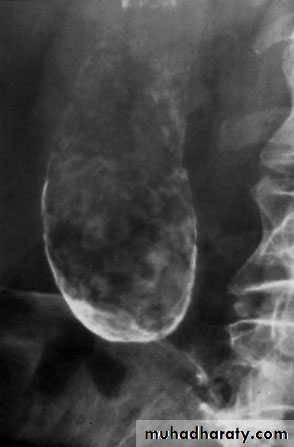

Gas in the gall bladder and gall bladder wall(Clostridium perfringens). Emergency surgery is indicated.